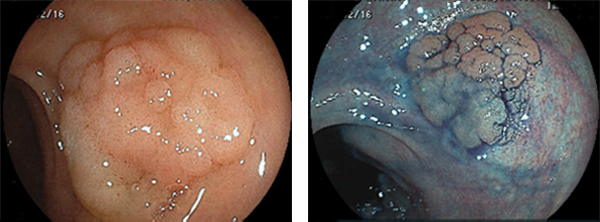

サイズの大きいLST(側方発育型腫瘍:低異形度腺腫)のEMR例

右:インジゴカルミン(色素)を散布し、病変の輪郭をはっきりさせます